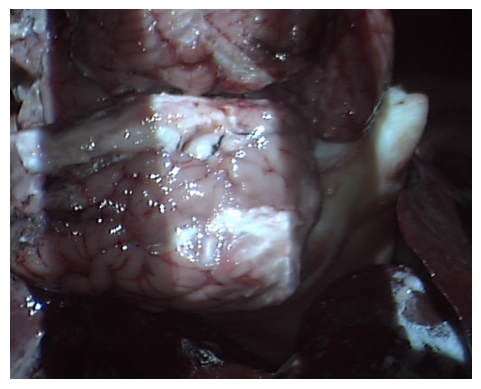

(a) The capture of a sheep’s liver using the dVRK laparoscope.

Refer to caption

(b) An example image captured which contains multiple ex vivo tissue.

Figure 2: Shown in (a) and (b) is the setup for the medical dataset collection. Image (a) shows an example of tissue captured using the dVRK laparascope. (b) does not contain projection patterns and would be fed as an input to the neural network.

Medical dataset: A medical dataset was created using the da Vinci Research Kit (dVRK) (Kazanzides et al. 2014) to extend the evaluation of the model onto real images. The dVRK was chosen as it is the research model of the surgical system that is used in clinical practice and commonly used for research in this field. A structured light projector was attached to a da Vinci camera arm and the stereo laparoscope of the machine was used to capture scenes with projected patterns on medical phantoms and ex-vivo organs from sheep, cows and chicken. Gray code was used for this dataset with 9 patterns. The decoding was performed using the three phase algorithm (Xu et al. 2022). A turning table was used to hold the objects and were rotated for multiple perspectives. Fig. 2 shows the setup and an example image which would be fed as the input to the neural network (an image without projection patterns).